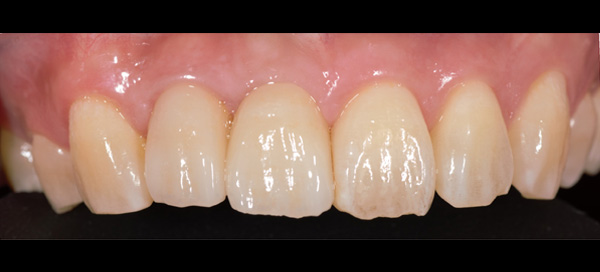

AFTER

| 年代・性別 | 50代 男性 |

|---|---|

| 主訴 | 右上下の歯が痛い |

| 治療期間 | 約12ヶ月 |

| 費用 | 2,500,000円 |

| 治療内容 | インプラント、骨造成、結合組織移植、セラミック修復 |

| 治療に伴うリスク | インプラント周囲炎 セラミックの破折、脱離 |

*キャンセルポリシーをご一読のうえご予約ください